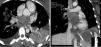

A healthy 25-year-old woman was admitted to the emergency department with a three-week history of gradual dyspnea on exertion, asthenia and weight loss. One week before admission, her dyspnea had worsened and had also presented at rest, with cough and hemoptysis, so she decided to seek medical attention. Physical examination revealed a mid-diastolic cardiac murmur. The transthoracic echocardiogram showed a large mass with irregular echogenicity filling the whole of the left atrium. Transesophageal echocardiography was performed and revealed the mass in the left atrium prolapsing into the left ventricle during diastole and causing mitral valve obstruction (Fig. 1A; Online Videos A–C). Continuous-wave Doppler ultrasound indicated severe mitral valve obstruction (mean gradient of 16mmHg) (Fig. 1B). The study also revealed extension into all the pulmonary veins (Fig. 1C). A computed tomogram of the thorax was performed and confirmed the diagnosis (Fig. 2; Online Video D). Cardiac surgery was performed with complete tumor resection (Fig. 3). The histopathological examination with immunohistochemical stain (Fig. 4A), hematoxylin–eosin stain (Fig. 4B) and electron microscopy (Fig. 4C) showed an undifferentiated pleomorphic sarcoma (pleomorphic malignant fibrous histiocytoma). The patient started chemotherapy and was discharged 17 days after surgery. Unfortunately, twenty days after discharge, she was readmitted to the hospital because of headache. Cranial computed tomography revealed multiple intracranial lesions suggestive of metastases. She underwent 10 sessions of holocranial radiotherapy. Six months after surgery she is alive but multiorgan metastatic disease has been demonstrated.

Figure 2.

Cardiac computed tomography (CT): CT images showing the tumor occupying almost the entire left atrial chamber and infiltrating the pulmonary veins.

Video D Cardiac computed tomography (CT): CT axial view showing the tumor occupying almost the entire left atrial chamber and extending into the pulmonary veins.